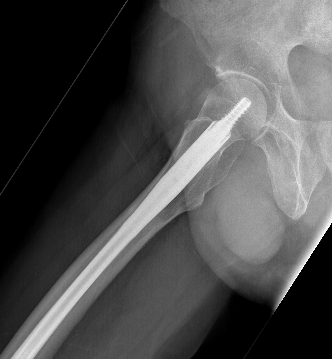

Nail aptypical 1Nail atypical 2

Femoral stress fractureFemoral Stress Fracture IMN

complete AFFNail AFF

1. Cephalomedullary nail

- be careful of bowed femurs in Asian women

2.  Lateral plate and screws

- high failure rate

- consider in setting of severe bowing

Koh et al. Bone Joint J 2017

- systematic review of 77 studies and 834 AFFs

- incomplete fractures: nonoperative treatment failed 47%

- incomplete fractures: surgery achieved union in 97%

- complete fractures: IMN nonunion rate 12.9%

- complete fractures: plate fixation nonunion rate 31%

- must discontinue bisphonates

- mean time to union 7 months post surgery